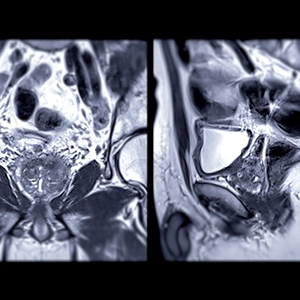

A prostate MRI is a safe, non-invasive imaging technique that uses magnets and radio waves to create highly detailed visualizations of the prostate gland. At our centers, we use advanced 3T MRI technology to deliver sharp images in less time and without the use of an endorectal coil, helping to ensure both accuracy and comfort for our patients.

Once your prostate MRI is complete, one of our board-certified radiologists will carefully review the images and look for any signs of concern, such as abnormal areas or changes in the prostate. These findings are complied into a detailed report and sent to your doctor.